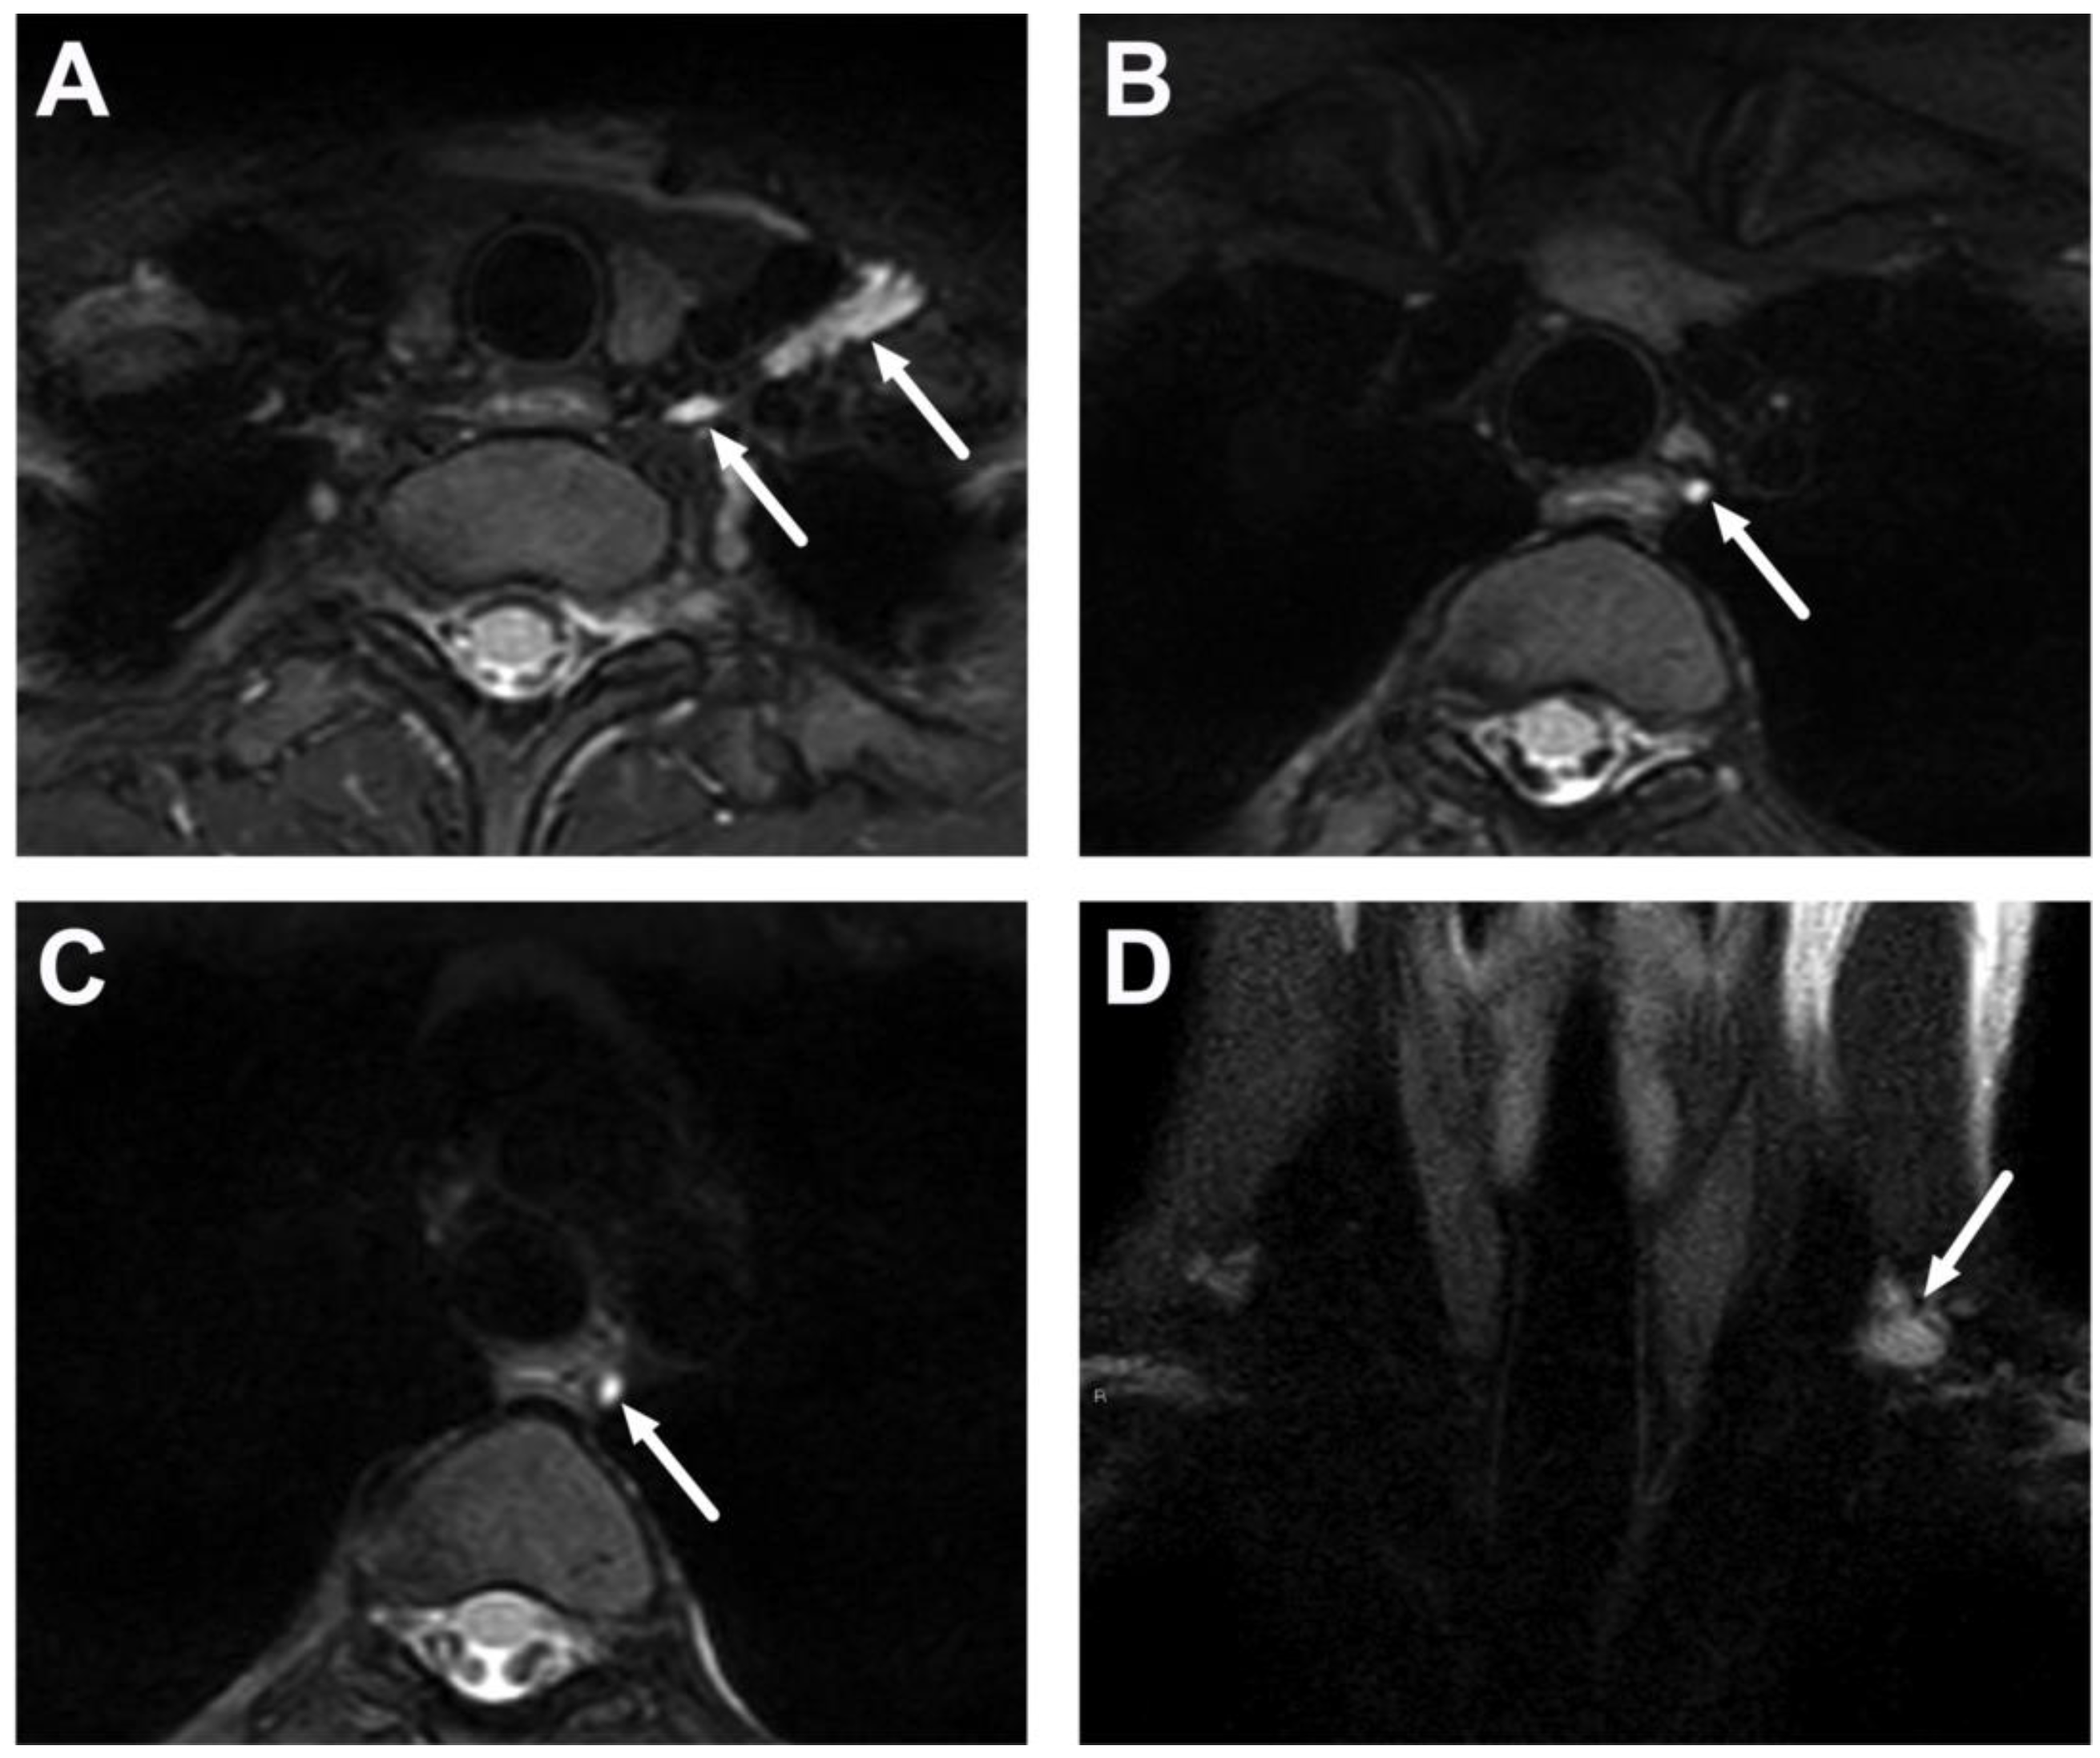

| Complications | Whole protocol | Abscess extending to multiple deep neck spaces, mediastinis, venous thrombosis, and airway compromise. | Detection of potentially life-threatening conditions. | Magnetic resonance angiography (MRA) or CECT may be needed to diagnose venous thrombosis; defining airway compromise is difficult. |